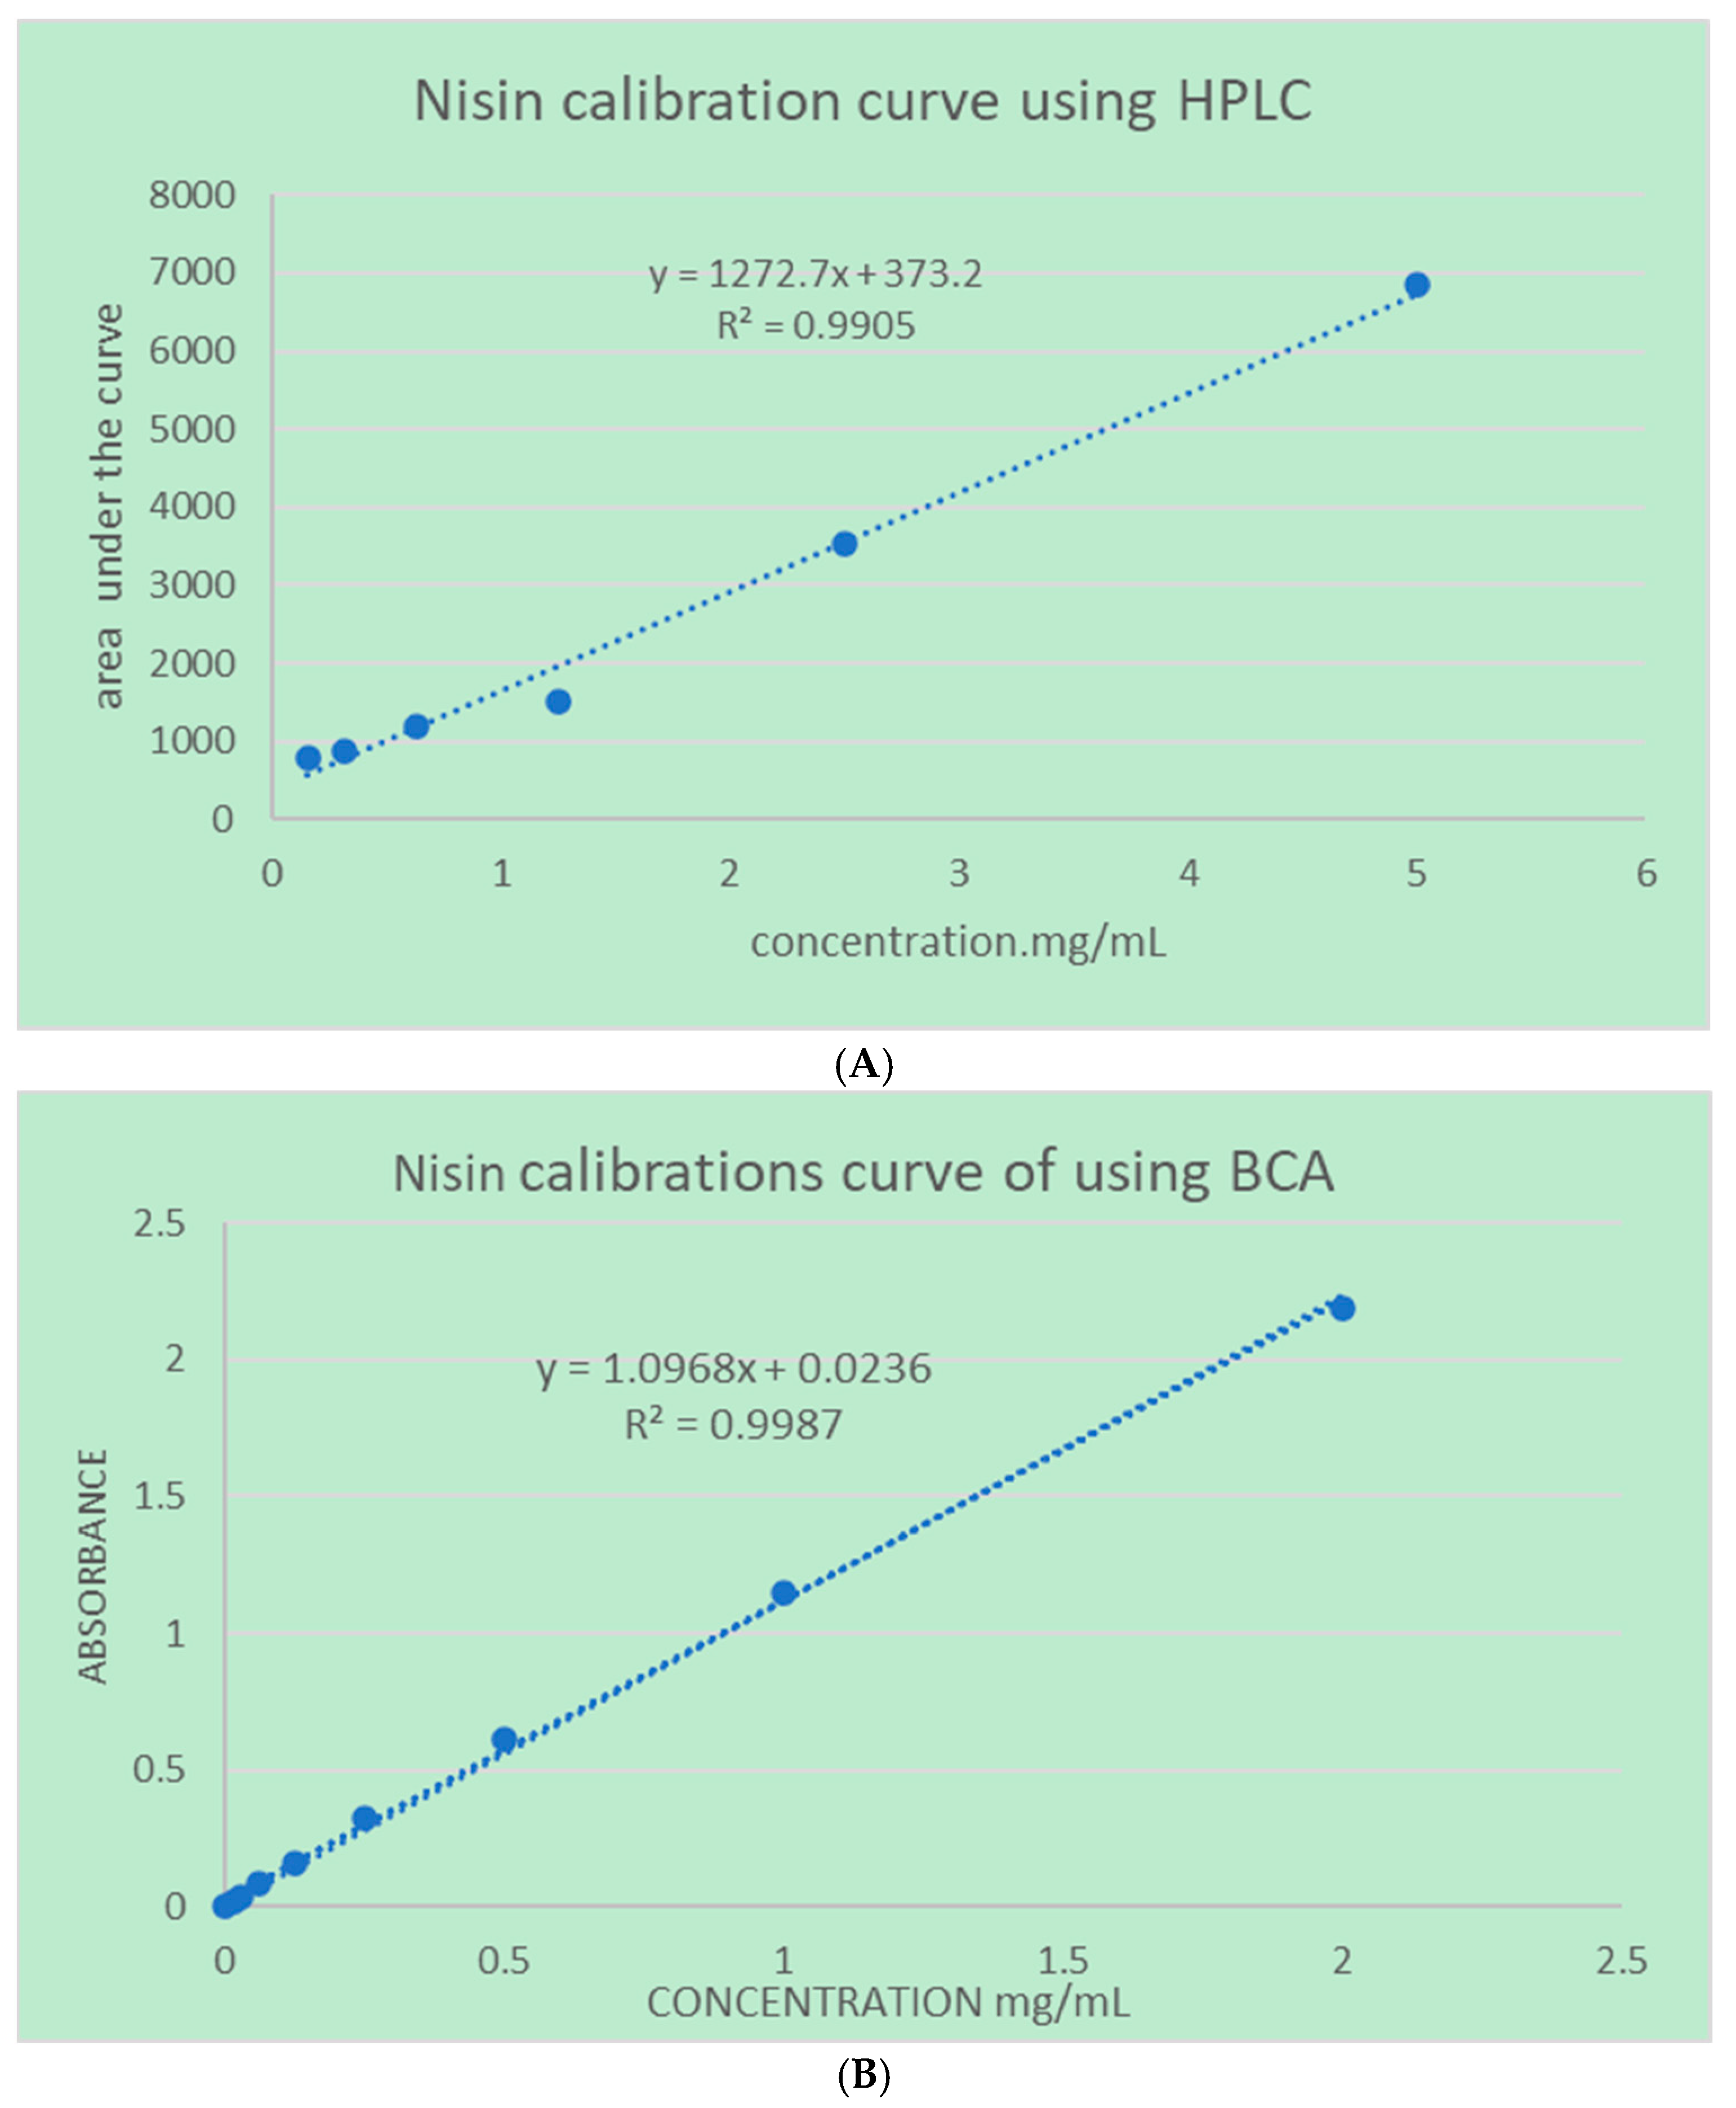

4.2.3. Quantifications Methods

5.1. Microfluidic Technology